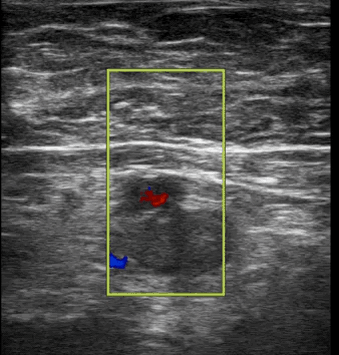

• Yes. Common femoral vein ultrasound for DVT - see below.

Clip 1- Right common femoral vein POCUS

• This is colour doppler over the common femoral vein (CFV) and artery (CFA).

Pulsatile flow is seen in the CFA but no flow is present in the CFV. Additionally there is hyperechoicity in the CFV suggestive of a thrombus.

• This is a proximal DVT, which has a positive likelihood ratio of +13 for PE in a patient in this scenario.